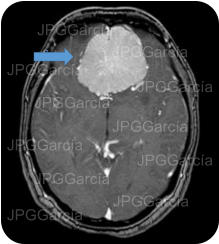

Posterior a una craneotomía cerebral izquierda y a la localización por anatomía de la lesión, se observa a la aspiración gentil salida de material purulento que hacen el diagnóstico de absceso cerebral